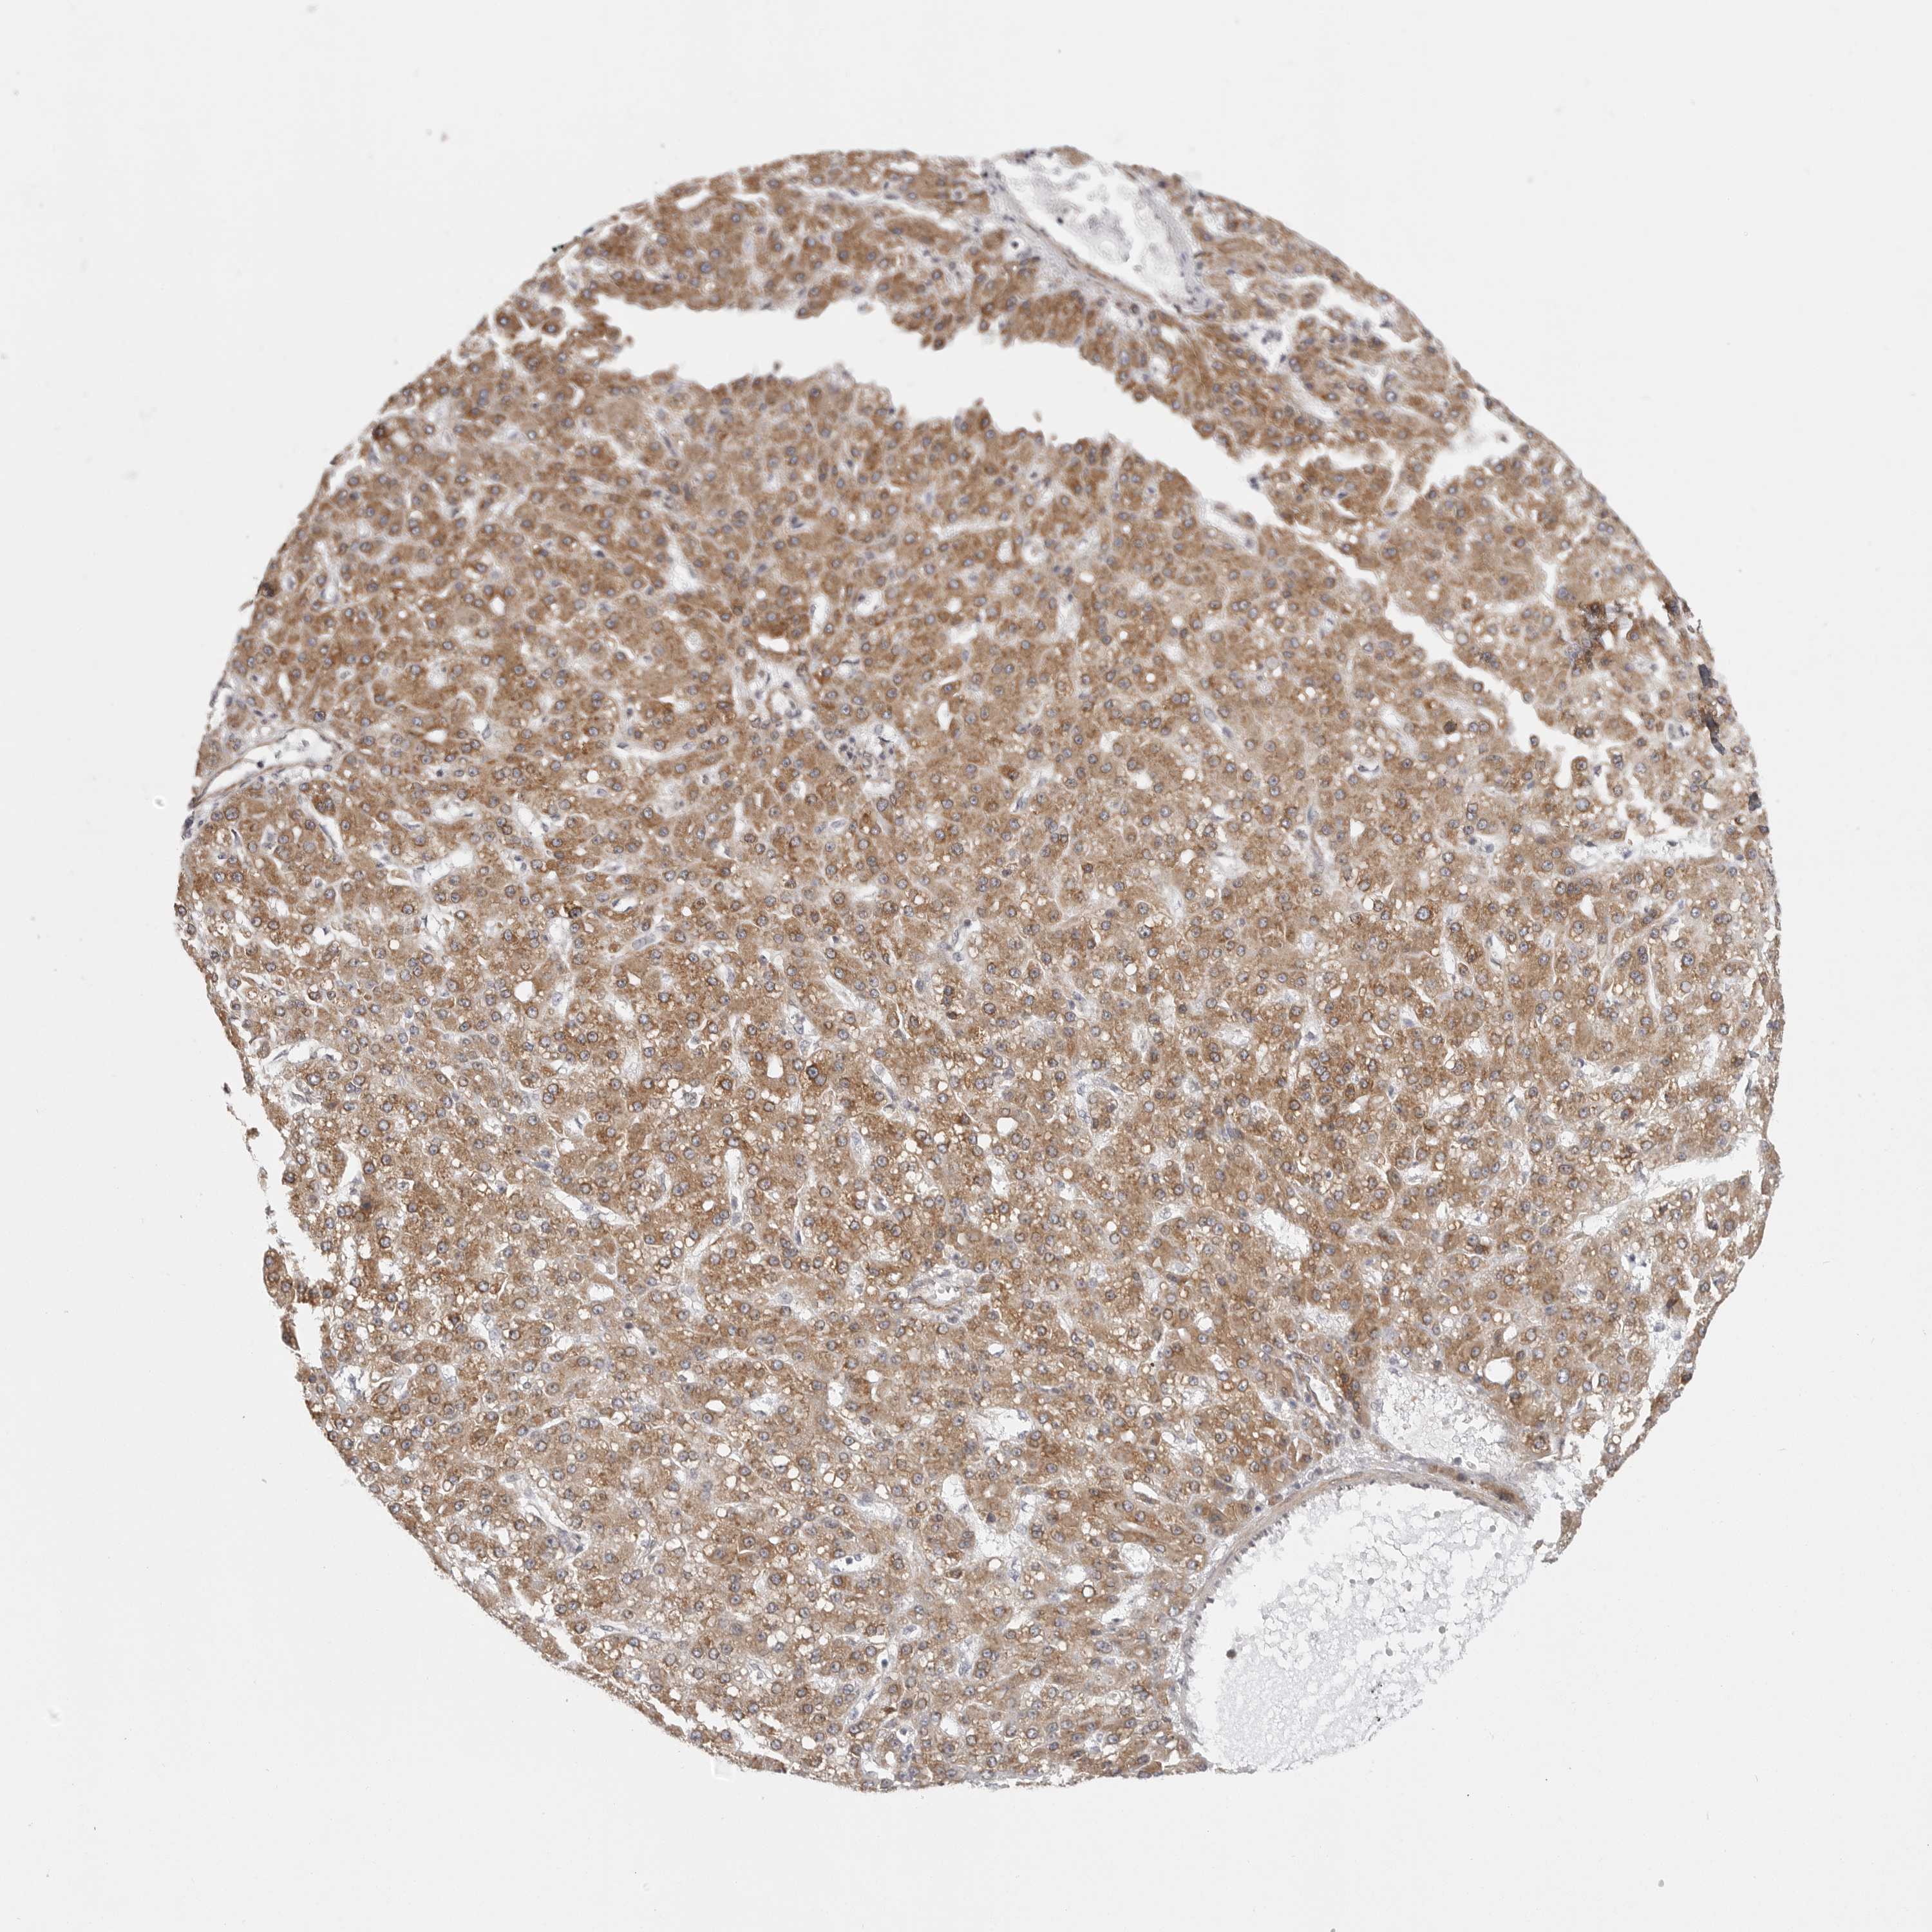

LIVER CANCER - Protein expressioni

A mouse-over function shows sample information and annotation data. Click on an image to view it in a full screen mode. Samples can be filtered based on level of antibody staining by selecting one or several of the following categories: high, medium, low and not detected. The assay and annotation is described here.

Note that samples used for immunohistochemistry by the Human Protein Atlas do not correspond to samples in the TCGA dataset.

Antibody stainingi

Antibody staining in the annotated cell types in the current human tissue is reported as not detected, low, medium, or high, based on conventional immunohistochemistry profiling in selected tissues. This score is based on the combination of the staining intensity and fraction of stained cells.

Each image is clickable and will lead to virtual microscopy that enables deeper exploration of all samples and also displays staining intensity scores, fraction scores and subcellular localization as well as patient and tissue information for each sample.

Antibody HPA027262

Antibody HPA078737

Staining

High

Medium

Low

Not detected

Intensity

Strong

Moderate

Weak

Negative

Quantity

>75%

75%-25%

<25%

None

Location

Nuclear

Cytoplasmic/membranous

Cytoplasmic/membranous,nuclear

Cholangiocarcinoma

Carcinoma, Hepatocellular, NOS